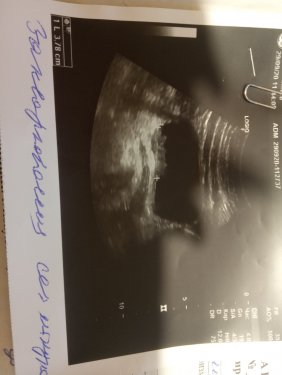

Добрый вечер! Обращаюсь в первый раз за помощью в такой форме,просто не знаю к кому ещё обратится. Мне нужна операция на мочевом пузыре, нашли две опухоли. Десять лет назад  я была прооперирована по такому же диагнозу Рак 1 стадии клеточно переходной. Я тогда была замужем и с финансами по этому вопросу было немного легче. Пару месяцев назад начали мучать боли  внизу живота,кровяное мочеиспускание,тошнота. Обратилась к врачу и на УЗО то подтвердили снова наявность двох образований на мочевом пузыре. Тех денег которые мне удалось собрать  своими  силами с дочкой и добрых людей не хватает на операцию и курс химии после неё. Поэтому очень прошу о помощи тех кто может помочь мне с этим вопросом. Так как почти 20 тыс грн это для нас найти сложно.  Я понимаю,что сейчас много людей  на этом зарабатывают деньги,но я надеюсь что эсть люди которые верят, и могут помочь. За каждую помощь от людей которые смогут помочь буду давать отчёт. Номер карты 5104 7700 2080 5943   ощадбанк. Деньги нужны на дополнитильные обследования МРТ, ренген с контрастом,это стоит около 3 тыс грн, потом через неделю операция и курс химии ,один флакончик которой стоит полторы тысячи грн, их надо на 10 дней может и больше,смотря какие рекомендации даст врач после операции. Мне ехать на 10 марта,поетому очень прошу помощи.  Я обращаюсь не только сюда,дочь писала в газеты,бросала обьявления о помощи, те люди которые смогли помочь плюс мы собрали нашими тоже силами то сума не большая совсем,хватит только на дополнитильные  обследования. Поетому очень прошу мне помочь!  Мои мульти кошельки  18L4CmyqyD16JyWgmUB67iUBf42tofCN9 /  0xdabf1e1adc767014d664ebbcbaec330c74028a23f

изображение_viber_2021-02-26_10-44-16.jpg

изображение_viber_2021-03-03_18-58-36.jpg

изображение_viber_2021-03-03_18-58-35.jpg

изображение_viber_2021-03-03_18-58-07.jpg